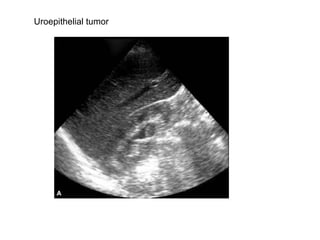

Uroepithelial tumor

Uroepithelial tumors. Tumor is shown in  the dilated renal pelvis (A) and at the pelviureteric junction